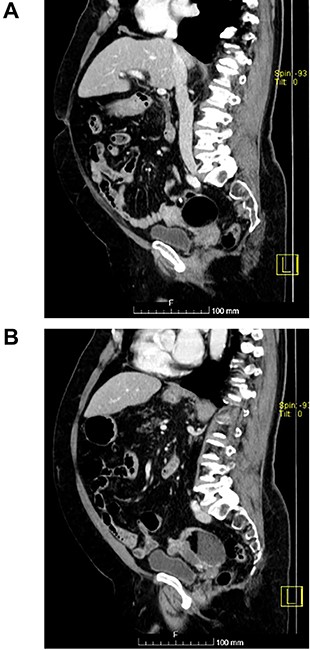

(A and B) Sagittal images of CT showing bilateral ovarian lesions.

The authors report the case of an asymptomatic 76-year-old female patient, referred to our Gynaecologic Clinic, due to suspicious adnexal lesions on a pelvic ultrasound (US). Menopause occurred at age 53. She had no history of abnormal uterine haemorrhage. Her menstrual cycles had been regular. She had had three gestations: two late abortions and one normal delivery, after which she breastfed. At our clinic, upon examination, vulva, vagina and cervix had no apparent lesions. The vaginal US revealed a right adnexal avascular cystic lesion of 65 mm, a left adnexal hyperechogenic cystic lesion of 60 mm, a normal sized uterus, a diffusely heterogeneous myometrium, an endometrial thickness of 8 mm and heterogenous intracavitary liquid. Her risk of ovarian malignancy assessment (ROMA) score was 28.1%, for a cut-off of 25.3%. Cancer antigen (CA) 125 and Human epididymis protein 4 (HE4) were 25.9 and 98.2, respectively. Lactate dehydrogenase (LDH), alpha fetoprotein (AFP) and beta human chorionic gonadotropin (bHCG) were normal. She subsequently had a magnetic resonance (MR) done (Fig. 1), which suggested bilateral ovarian teratoma. She also had an upper digestive endoscopy and a hysteroscopy that were normal and a computed tomography (CT) done (Figs 2–4) that showed: in the right adnexal region, a solid well-demarcated tumoural mass of 55 mm, with predominantly fat density, peripherical calcifications and a central hyperdense image (similar to a tooth), suggestive of a teratoma; in the left adnexal region, a predominantly cystic bilobated tumoural mass of 65 mm, with peripherical calcifications and an area of fat density, also suggestive of teratoma; and no additional disease. This case was presented at our Multidisciplinary Tumour Board, where surgery was proposed. Thus, she underwent exploratory laparotomy, peritoneal washing, total hysterectomy and bilateral adnexectomy, which ran uneventfully. Intra-operative frozen section excluded ovarian malignancy. She had an uneventful recovery and was discharged home on the third post-operative day. The pathological report revealed bilateral mature cystic teratoma with representation of the three germinative layers and thyroid parenchymal tissue (struma ovarii) (Fig. 5). Both ovaries were atrophic and had a cavitated lesion covered by respiratory epithelium with hyaline cartilaginous, adipose, smooth muscular and mucosa-associated lymphoid tissues (positivity for CD3 and CD20), seromucinous glands and thyroid follicles (homogenous positivity for thyroglobulin). Thyroid follicles were well differentiated, without features of malignancy. Fallopian tubes were normal. There were also uterine leiomyomas and a mucosal endocervical polyp. She was euthyroid and had a thyroid US done, which was normal. Follow-up at first post-operative month, remaining asymptomatic.